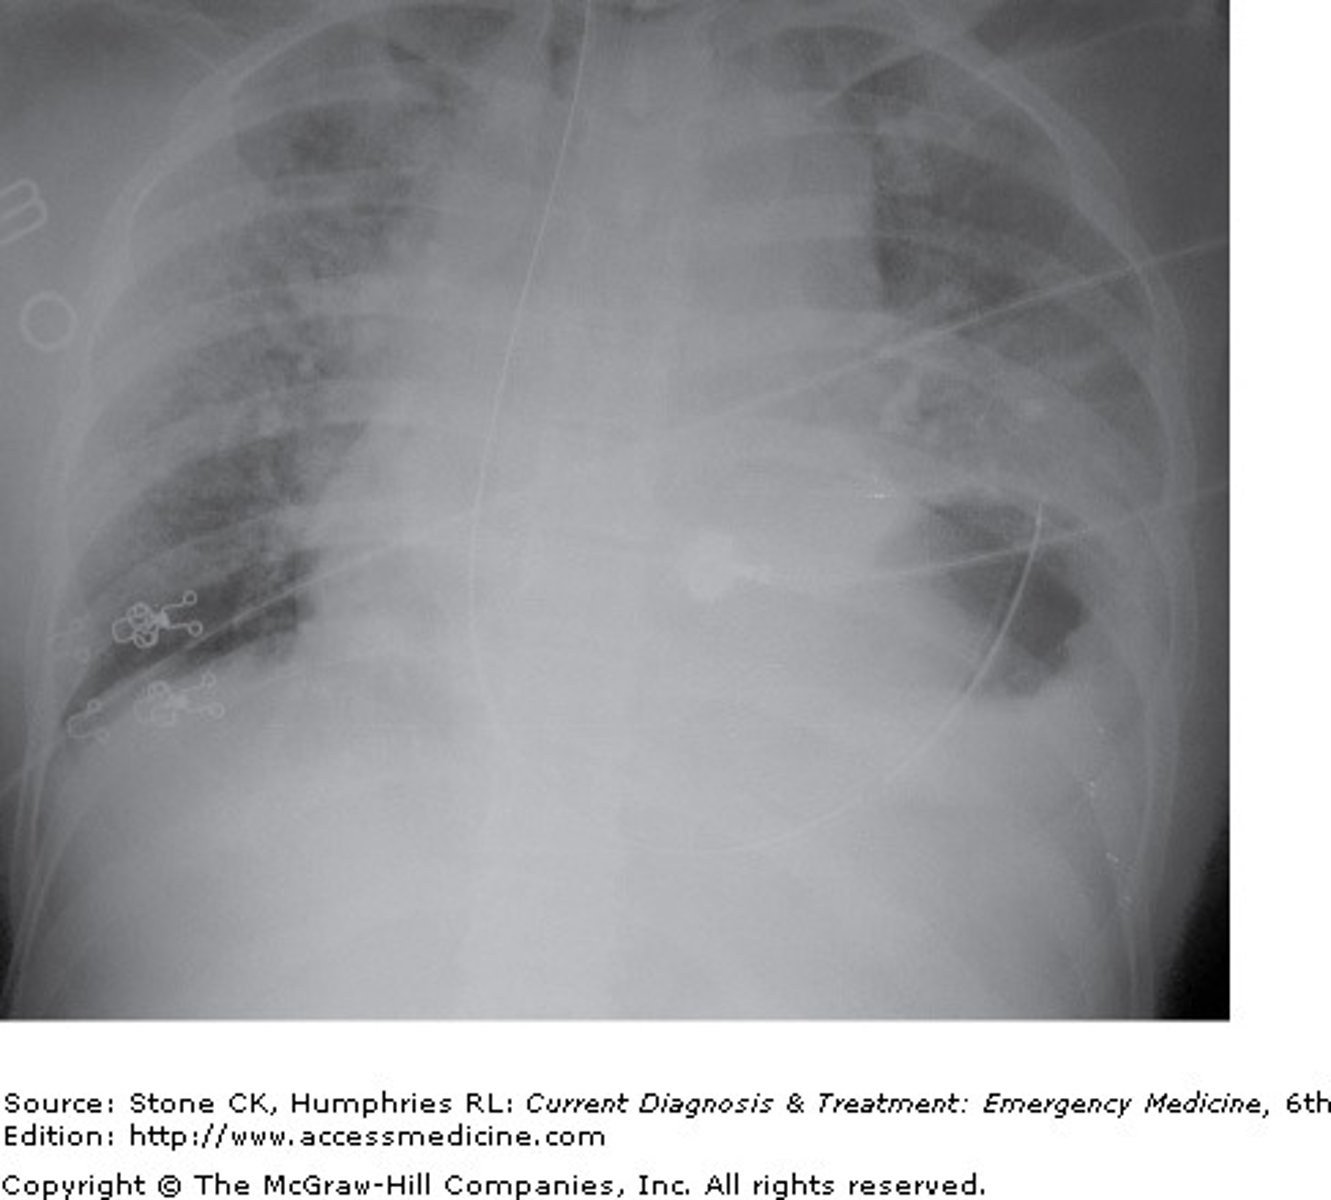

A 44-year-old female is involved in a motor vehicle accident, during which she suffered blunt trauma to the left chest and abdomen from the car door. She presents via rescue with marked dyspnea, tachypnea, and an oxygen saturation of 87% on room air. You obtain the chest x-ray shown. Based on the following x-ray, what is the diagnosis?

Diaphragmatic rupture is often the result of direct injury to the diaphragm or increased intra-abdominal or intrathoracic pressure. Patient symptoms are often the result of impaired lung expansion and decreased oxygenation. Additional symptoms may include bowel obstruction or other nonspecific bowel complaints. The chest x-ray shows elevation and irregularity of the left diaphragmatic border, with decreased left lung volume. Also of note is a widened mediastinum, which may suggest additional injury, including to the aorta. Lung markings extend through the lung space, which is not consistent with a hemothorax or pneumothorax. Evaluation for a pericardial effusion and/or pericarditis should be performed on this patient, based on the history, with evaluation including echocardiography and EKG. The typical x-ray result for pericardial effusion is termed a "water bottle" heart. However, this would be difficult to assess in the setting of a diaphragmatic rupture. Cor pulmonale is not associated with trauma, and is due to lung disease or pulmonary vascular disease.